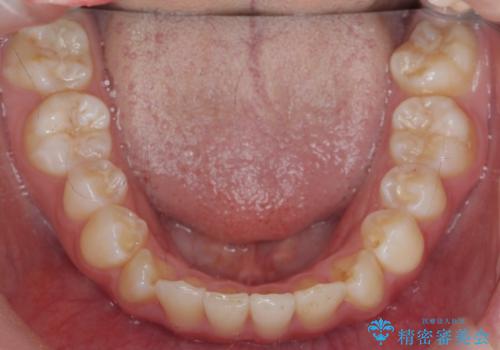

インビザラインライトで行う短期マウスピース矯正治療

- 前歯のガタつきを並べたいたいと、矯正治療を希望され来院されました。

とにかく短期間で前歯だけの治療を行いという希望が強く、全体矯正と前歯だけの部分矯正の仕上がりのイメージを確認したのち14枚のマウスピースで前歯のみの矯正治療を行っていくこととしました。

インビザラインライトは軽度なガタつきや傾斜の改善に用いられる全14枚のマウスピース矯正です。